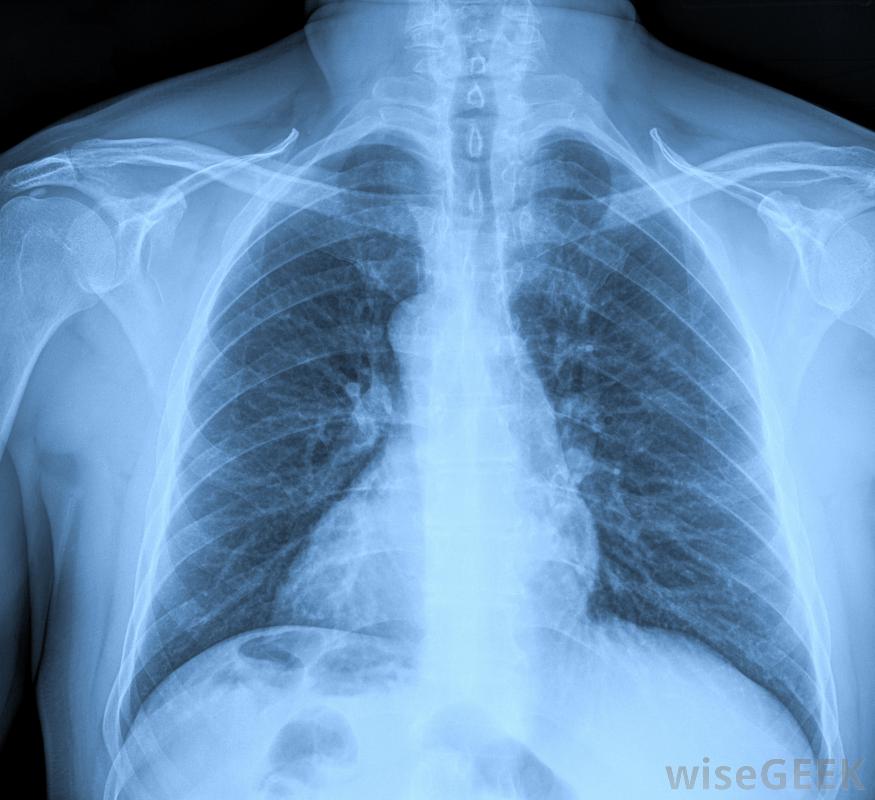

经口气管插管时,医生、护理人员或高级心脏生命支持(ACLS)提供者站在病人的头上,倒立在病人的解剖结构上,用喉镜的刀片将舌头和会厌抬开。会厌保护气管顶部或气道,防止意外进入食物或液体。当被提起并让开时,可以通过照亮的喉镜刀片和插入气管的呼吸管来识别气管顶部的声带。因为食道-胃部的导管-与气管相邻,尝试性的经口气管插管可以很容易地将呼吸管引入食道而不是气管。有几种类型的评估用于确认呼吸管的正确放置,包括在适当的位置倾听呼吸声和胸部x光片(如有)。

呼吸管被固定住将靠近气管末端的一个小灯泡充气,使其处于适当的位置。将导管从患者口中伸出的地方用胶带固定,并进行额外的捆扎以进一步固定气管插管。如上所述,气管插管的正确放置总是通过尽快的胸部x光片来确认。

胸部x光片用于确认呼吸管的正确放置。